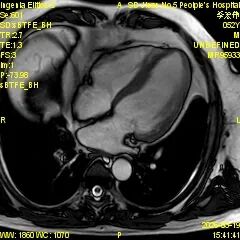

为进一步提升心血管疾病精准诊断水平,满足临床诊疗和患者就医需求,济南市第五人民医院影像科精心筹备、多措并举,顺利开展心脏磁共振(CMR)新技术,目前已完成心脏磁共振检查近30例,取得了良好效果,标志着医院心血管影像诊断能力迈上新台阶。

心脏磁共振被誉为评估心脏结构、功能及心肌组织特征的 “金标准”,具有无创、无辐射、多参数、精准度高等优势,可以为心肌病、冠心病、瓣膜病、先天性心脏病等疾病提供全面、客观的影像学依据,对临床制定治疗方案、评估预后具有重要意义。